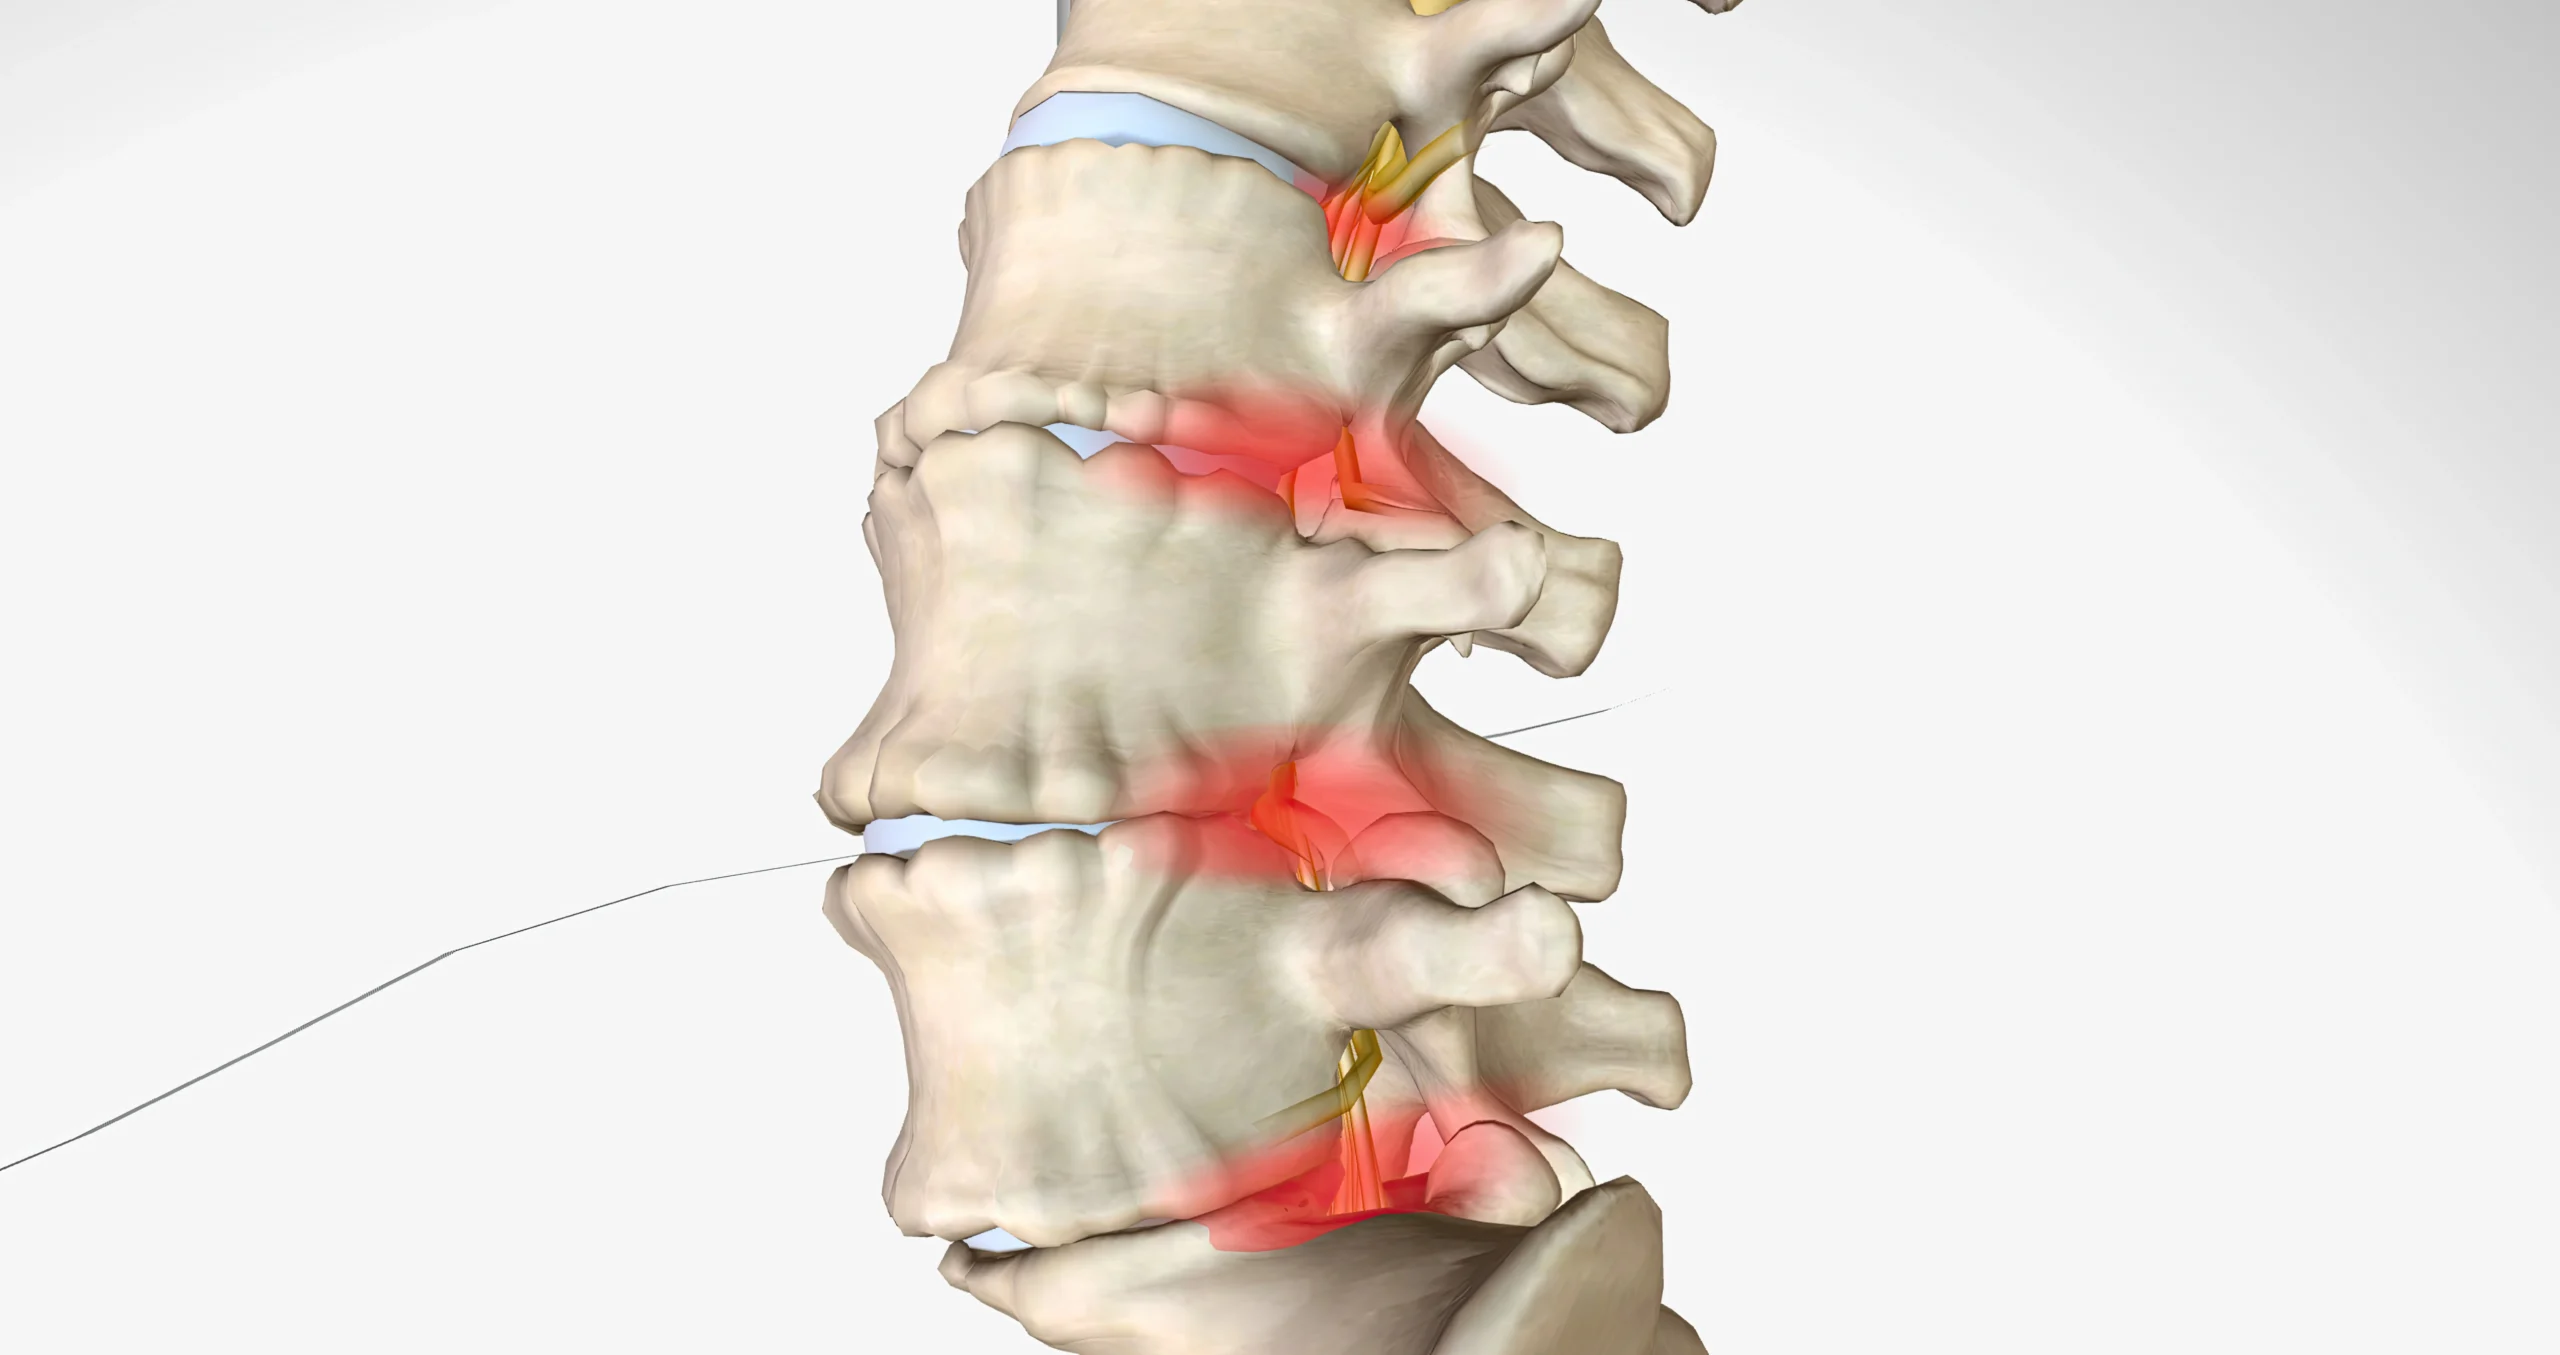

Selain kekurangan cairan dalam tubuh atau kekurangan mineral tertentu, kondisi lain seperti menyempitnya rongga antartulang belakang (stenosis spinal) dan terjepitnya saraf tulang belakang (hernia nukleus pulposus/HNP) juga dapat menyebabkan kram pada kaki.

Kekurangan mineral seperti kalium, kalsium, atau magnesium dalam tubuh dapat menyebabkan otot menjadi rentan terhadap kram. Selain itu, beberapa obat untuk tekanan darah tinggi dapat meningkatkan frekuensi buang air kecil, yang dapat mengurangi kadar mineral penting ini dalam tubuh.